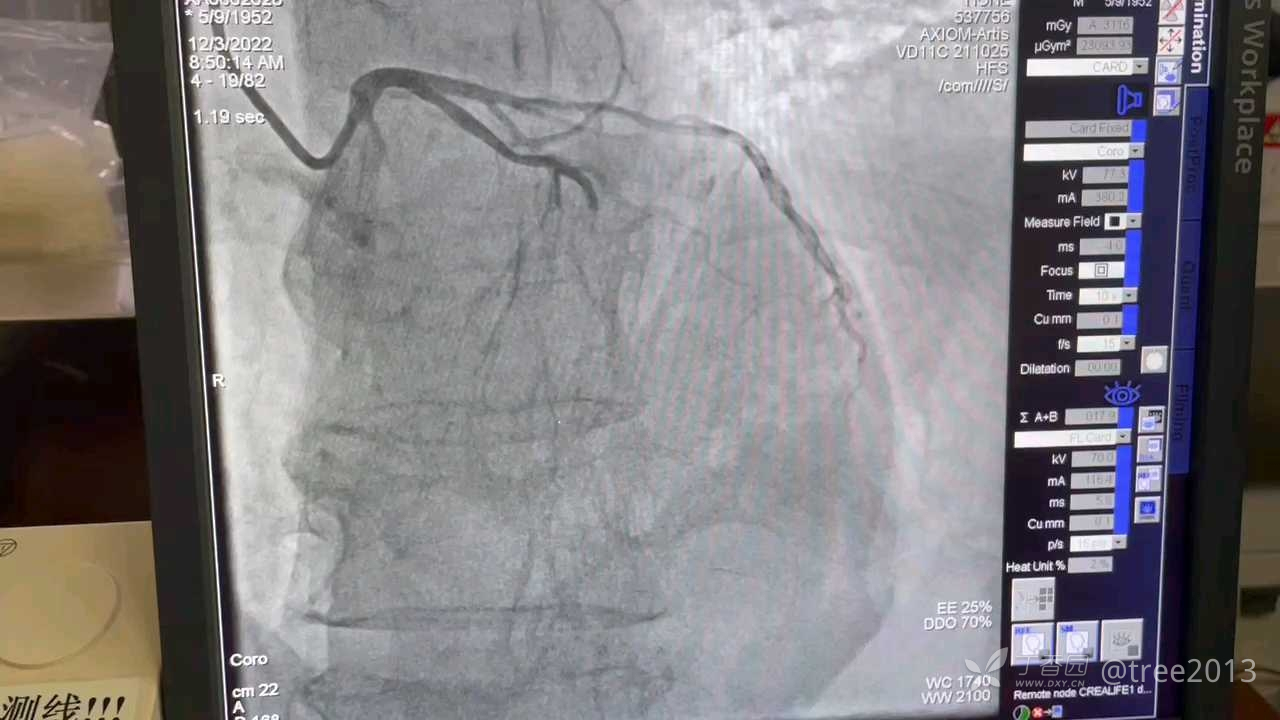

处理:立即给予嚼服阿司匹林及氯吡格雷各300mg,急查心梗三项、D二聚体、血常规、电解质、凝血功能、肝素功能等,向家属交待病情后,立即入导管室,造影示:前降支中段闭塞,给予行球囊扩张术,术后患者症状消失,病情稳定。

造影结果如下: